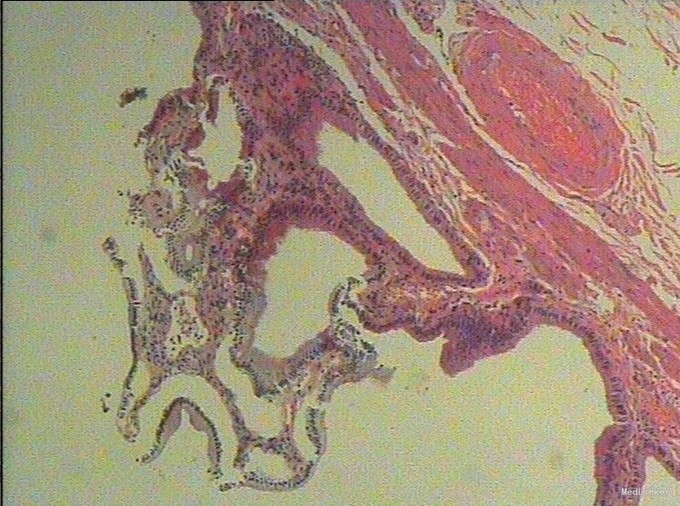

随访:术后病理示:(右肝肿物)送检肝组织部分呈结节状增生,结节间见粗细不等的纤维间隔,其内见血管增生,少量淋巴细胞及浆细胞浸润,符合肝局灶性结节状增生(FNH)。 讨论:肝局灶性结节增生(FNH)是肝内第二常见良性肿瘤,一般无临床症状,影像学表现,MRI上T1WI和T2WI与周围肝实质信号相近,增强扫描动脉期明显强化,若存在中央瘢痕,则中央瘢痕不强化,门脉期及静脉期强化程度减退,中央瘢痕则呈延迟强化。FNH需与肝癌和肝腺瘤鉴别,本例即误诊为肝癌,若存在中央瘢痕,则诊断较容易。